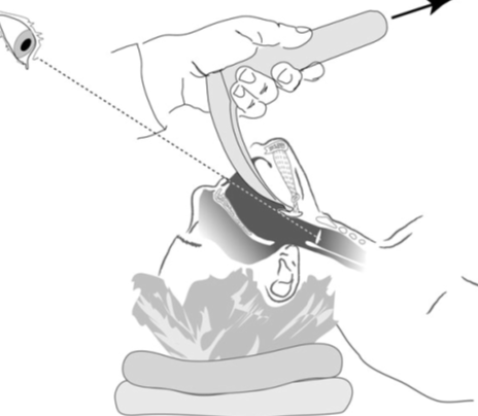

- For adults size the airway from the tragus of the ear to the edge of mouth

- Insert upside down and rotate backwards over the tongue

- In children place the device in the ‘right way round’ to avoid trauma to the upper oropharynx